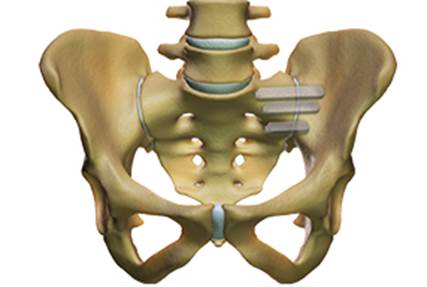

Surgical treatment of the painful SI joint is indicated only in cases where conservative therapy has failed for longer than 6 months. If the chronic SI joint pain persists, minimally invasive surgery can be performed: it consists of the percutaneous placement of three triangular titanium implants that block the ilium and sacrum bones, blocking the SI joint in all its degrees of freedom.

In recent years, more than 30,000 procedures have been performed worldwide. Clinical studies show a significant improvement in a patient’s quality of life after surgery compared to patients treated without surgery.

Characterization of percutaneous surgical fusion of the left sacro-iliac

joint by means of 3 titanium implants with triangular profile.

Dr. Morgenstern is an accredited surgeon for the percutaneous fusion of the sacroiliac joints.